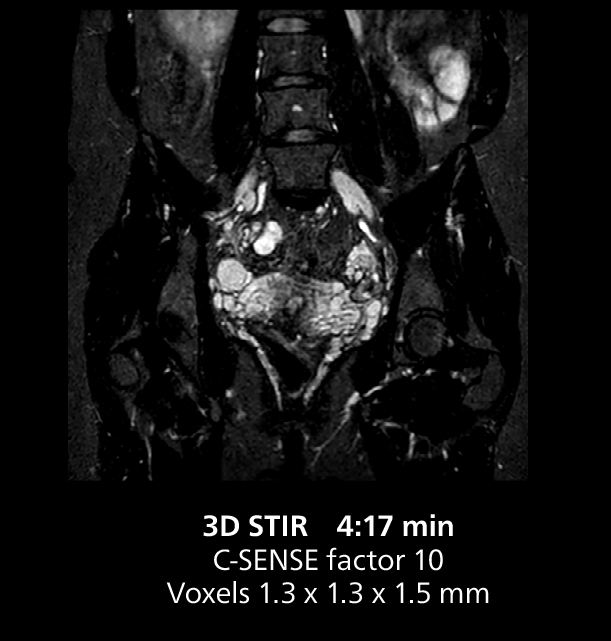

This MRI case illustrates good resolution and imaging quality obtained within reasonable scan times using the MR 5300 1.5T system with the anterior torso cardiac coil that allows use of a large field of view (FOV).

The MR 5300 with Compressed SENSE is up to 50%** faster for many exams. It can provide routine exams in less than 5 minutes and whole-body exams in less than 20 minutes. Saint-Augustin has taken advantage of that speed to create highly efficient protocols. The hospital’s standard stroke protocol is just about 8 minutes, and standard ENT, prostate PIRADS staging, and endometriosis studies all clock in at just about 10 minutes.***

“Having this speed is better for patients as well. For example, if a patient has a fibroma, I like to include a post-gadolinium scan, because the enhancement pattern helps in diagnosis. Without that sequence, we sometimes need another appointment to perform additional scanning, but I really prefer to do it all in just one scan session. So, adding that post-gadolinium sequence is more valuable to me than reducing exam length.”